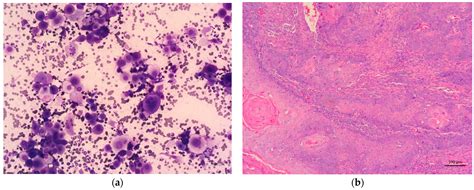

Association Between Cytological and Histopathological Diagnoses of ...

mdpi.com